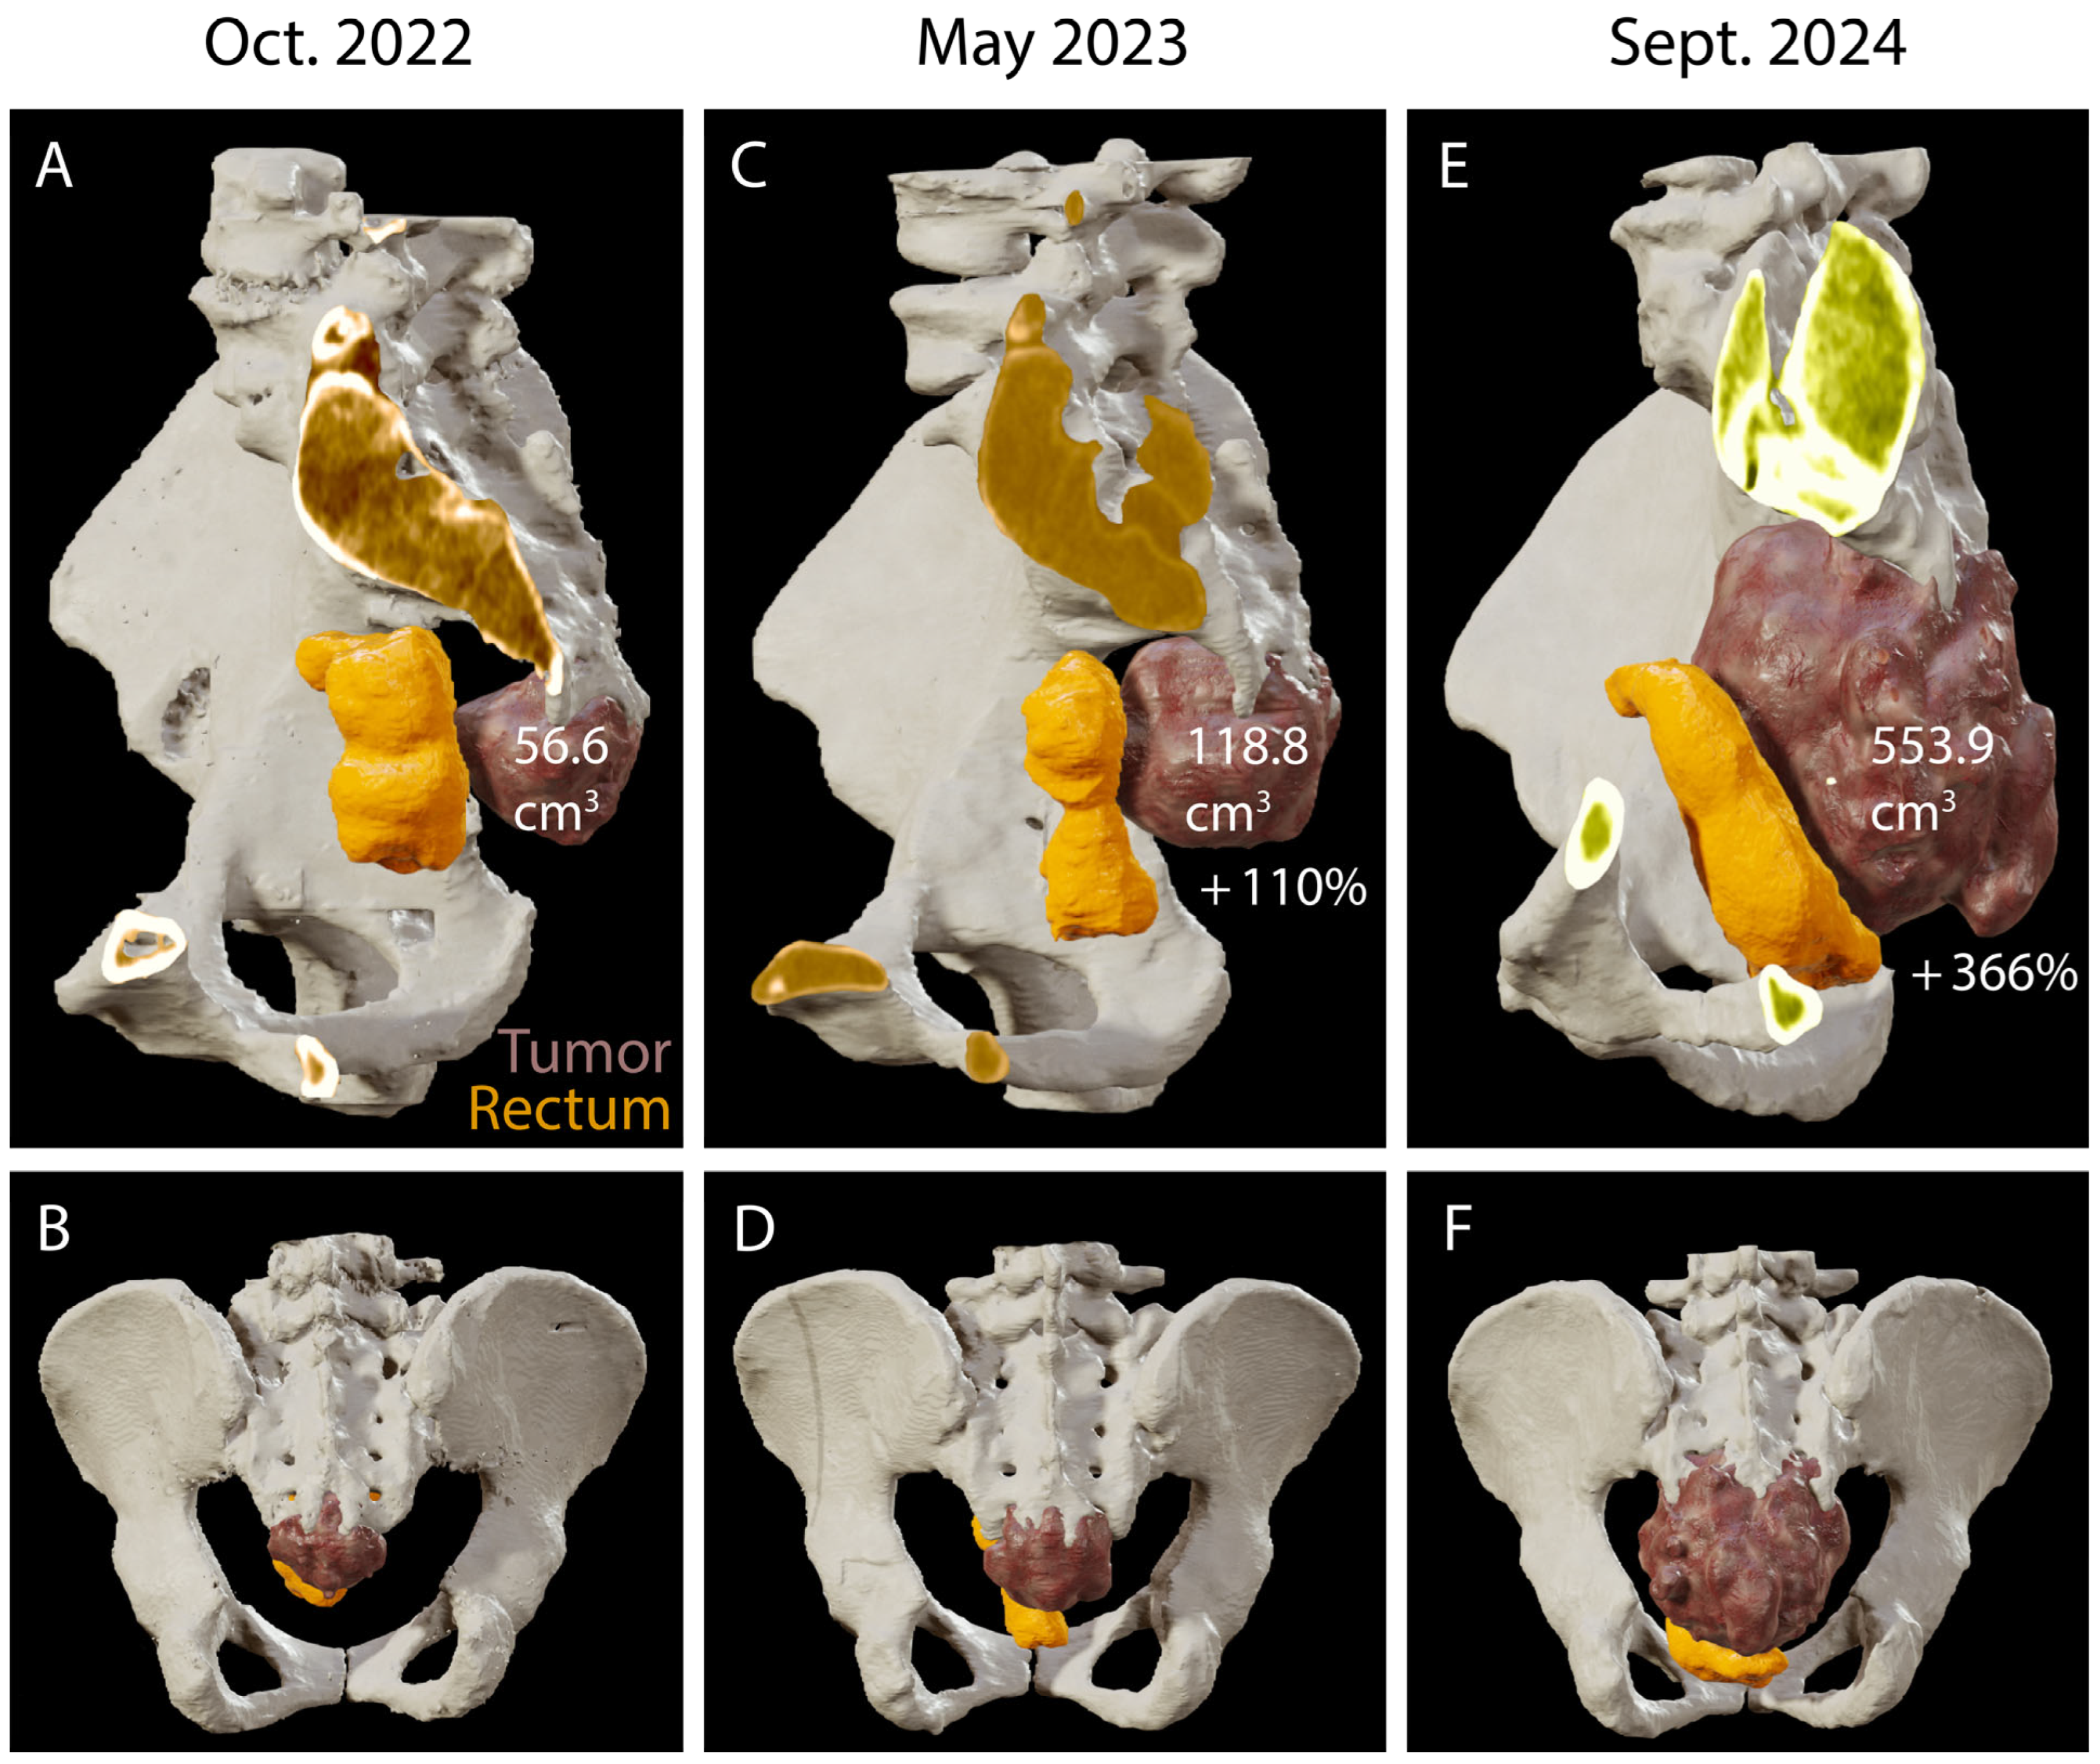

4. Results: Illustrative Case

4.1. Clinical Elements

4.2. Preoperative Planning